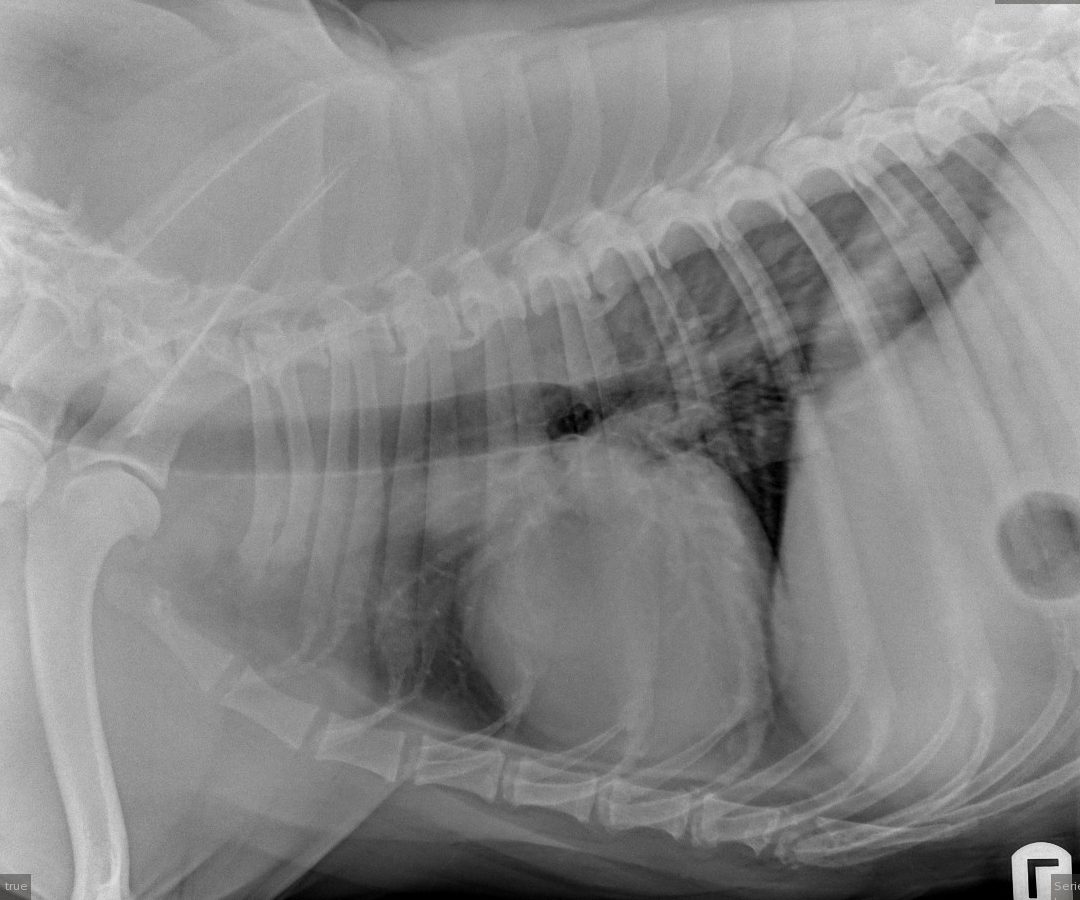

Bobs for dogs x ray top, A Visual Guide to GI Obstruction on Radiographs top

A Visual Guide to GI Obstruction on Radiographs

A Visual Guide to GI Obstruction on Radiographs

Thought you would find the radiographs of my pet rat Bob s badly sprained back right leg interesting. r Radiology top, Thought you would find the radiographs of my pet rat Bob s badly sprained back right leg interesting. r Radiology top, Newfoundland Dog Health Center top, X ray of dog lateral view with Gastric dilatation volvulus GDV or stomach twists Double bubble pattern indicates stomach torsion has occurred Veterinary medicine and Veterinary anatomy Concept. Stock... top, A Visual Guide to GI Obstruction on Radiographs top, Newfoundland Dog Health Center top, How Nestle s leg almost got amputated Dr Phil Zeltzman s Blog top, Radiography of the Small Animal Skull Temporomandibular Joints Tympanic Bullae Today s Veterinary Practice top, Loving Paws Pet Clinic Low stress veterinarian in Savoy IL X rays top, A Visual Guide to GI Obstruction on Radiographs top, Small Animal Elbow and Antebrachium Radiography Today s Veterinary Practice top, Understanding X rays can save dollars and lives WCVM Today Western College of Veterinary Medicine University of Saskatchewan top, A Visual Guide to GI Obstruction on Radiographs top, Radiography of the Small Animal Skull Temporomandibular Joints Tympanic Bullae Today s Veterinary Practice top, You removed how much of Mimi s jaw Dr Phil Zeltzman s Blog top, Dog X rays Variety of Radiographs Taken on Dogs top, Dog X rays Variety of Radiographs Taken on Dogs top, X ray Dog Anterior Image Photo Free Trial Bigstock top, X Ray Normal Forelimb Dog Stock Photo 689852953 Shutterstock top, DOG BOWEL OBSTRUCTION X RAY Stock Photo Image of skeleton pain 30050362 top, xray of dogs chest showing heart disease Stock Photo Alamy top, Bobby Bob Bob Tamara Kenneally Photography top, BOBs Kennels top, Radiographs for Dogs Bioscint top, Dog X rays Variety of Radiographs Taken on Dogs top, Pets will eat the strangest things top, Dog X rays Variety of Radiographs Taken on Dogs top, Lateral X ray Radiograph Left Forelimb Puppy Stock Illustration 1344763586 Shutterstock top, Top 5 Tips on Radiographic Diagnosis of Obstructive Foreign Bodies top, Dog X rays Variety of Radiographs Taken on Dogs top, Right Lateral Chest X ray Radiograph Dog Stock Illustration 1337012921 Shutterstock top, Dog X rays Variety of Radiographs Taken on Dogs top, Abdominal X Rays Made Easy top, Old Chapel Veterinary Clinic Canine elbow dysplasia ED is a disease of the elbows of dogs caused by growth disturbances in the elbow joint. Elbow dysplasia is most often seen in top, Hi Ferg swallowed a piece of flat rubber ball about 1 x2.5 a week ago. She has been asymptomatic. Xrays were taken and radiologist. PetCoach top.

Thought you would find the radiographs of my pet rat Bob s badly sprained back right leg interesting. r Radiology top, Thought you would find the radiographs of my pet rat Bob s badly sprained back right leg interesting. r Radiology top, Newfoundland Dog Health Center top, X ray of dog lateral view with Gastric dilatation volvulus GDV or stomach twists Double bubble pattern indicates stomach torsion has occurred Veterinary medicine and Veterinary anatomy Concept. Stock... top, A Visual Guide to GI Obstruction on Radiographs top, Newfoundland Dog Health Center top, How Nestle s leg almost got amputated Dr Phil Zeltzman s Blog top, Radiography of the Small Animal Skull Temporomandibular Joints Tympanic Bullae Today s Veterinary Practice top, Loving Paws Pet Clinic Low stress veterinarian in Savoy IL X rays top, A Visual Guide to GI Obstruction on Radiographs top, Small Animal Elbow and Antebrachium Radiography Today s Veterinary Practice top, Understanding X rays can save dollars and lives WCVM Today Western College of Veterinary Medicine University of Saskatchewan top, A Visual Guide to GI Obstruction on Radiographs top, Radiography of the Small Animal Skull Temporomandibular Joints Tympanic Bullae Today s Veterinary Practice top, You removed how much of Mimi s jaw Dr Phil Zeltzman s Blog top, Dog X rays Variety of Radiographs Taken on Dogs top, Dog X rays Variety of Radiographs Taken on Dogs top, X ray Dog Anterior Image Photo Free Trial Bigstock top, X Ray Normal Forelimb Dog Stock Photo 689852953 Shutterstock top, DOG BOWEL OBSTRUCTION X RAY Stock Photo Image of skeleton pain 30050362 top, xray of dogs chest showing heart disease Stock Photo Alamy top, Bobby Bob Bob Tamara Kenneally Photography top, BOBs Kennels top, Radiographs for Dogs Bioscint top, Dog X rays Variety of Radiographs Taken on Dogs top, Pets will eat the strangest things top, Dog X rays Variety of Radiographs Taken on Dogs top, Lateral X ray Radiograph Left Forelimb Puppy Stock Illustration 1344763586 Shutterstock top, Top 5 Tips on Radiographic Diagnosis of Obstructive Foreign Bodies top, Dog X rays Variety of Radiographs Taken on Dogs top, Right Lateral Chest X ray Radiograph Dog Stock Illustration 1337012921 Shutterstock top, Dog X rays Variety of Radiographs Taken on Dogs top, Abdominal X Rays Made Easy top, Old Chapel Veterinary Clinic Canine elbow dysplasia ED is a disease of the elbows of dogs caused by growth disturbances in the elbow joint. Elbow dysplasia is most often seen in top, Hi Ferg swallowed a piece of flat rubber ball about 1 x2.5 a week ago. She has been asymptomatic. Xrays were taken and radiologist. PetCoach top.